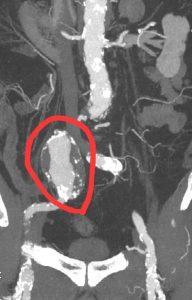

подвздошная артерия

В Раменской больнице провели уникальную операцию по спасению пациента с гигантской аневризмой. Прорыв в сосудистой хирургии!